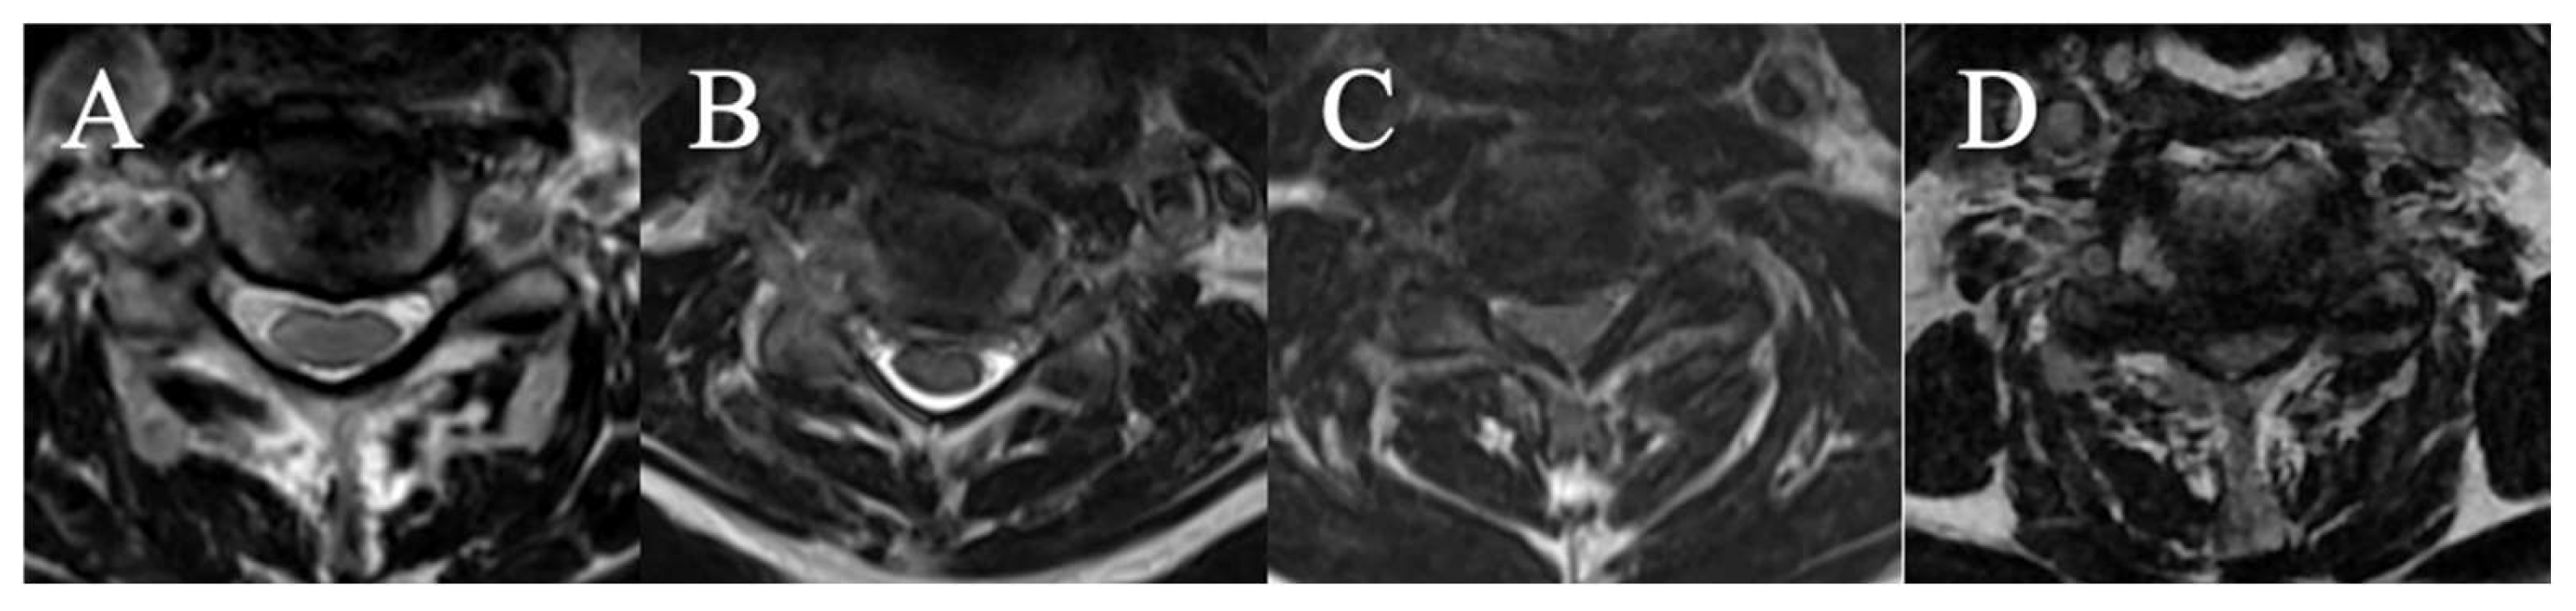

4 grades have been selected on axial slice (Figure 3)

(A) CSF visible anteriorly and posteriorly

(B) CSF erased anteriorly or posteriorly

(C) CSF erased anteriorly and posteriorly but root cisterns still visible

(D) Totally erased cisterns – no CSF visible on the slice

Figure 3. (A): CSF visible anteriorly and posteriorly ; (B) CSF erased anteriorly or posteriorly ; (C) CSF erased anteriorly and posteriorly but root cisterns visible ; (D) Totally erased cisterns.